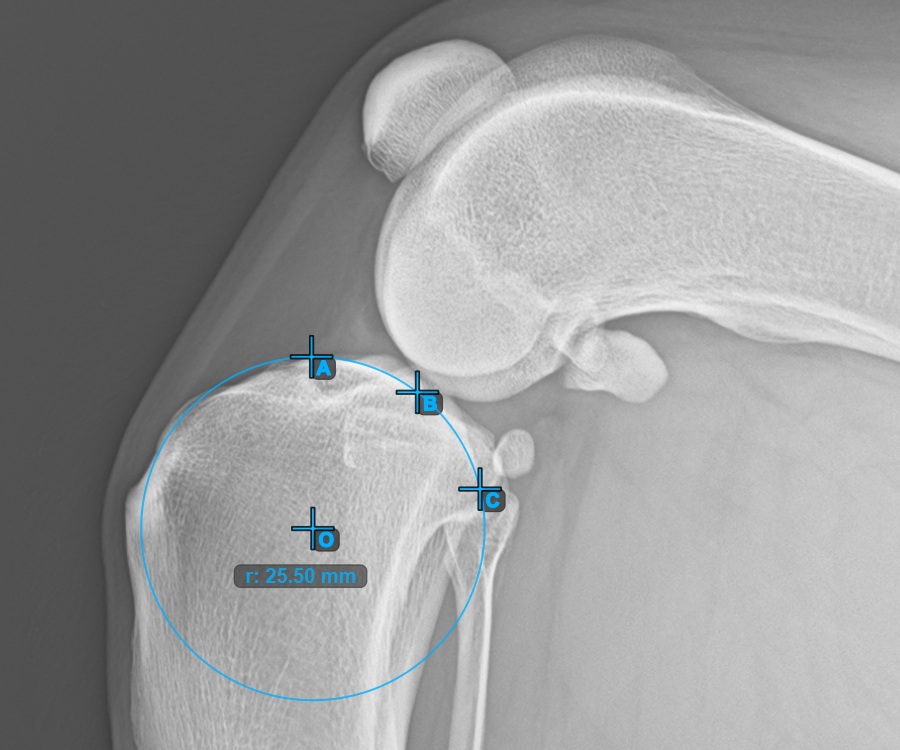

Continue by marking the three points on the articular surface of the first Condylus Femoris.

Mark the three points on the main condylus of the femoral bone (Condylus Femoris). Regardless of the order, make sure to mark the most cranial point, the most caudal point and the midpoint of the Condylus Femoris. A circle will be automatically constructed based on the three placed points.

The image below represents a typical placement of the three points on the first Condylus Femoris.